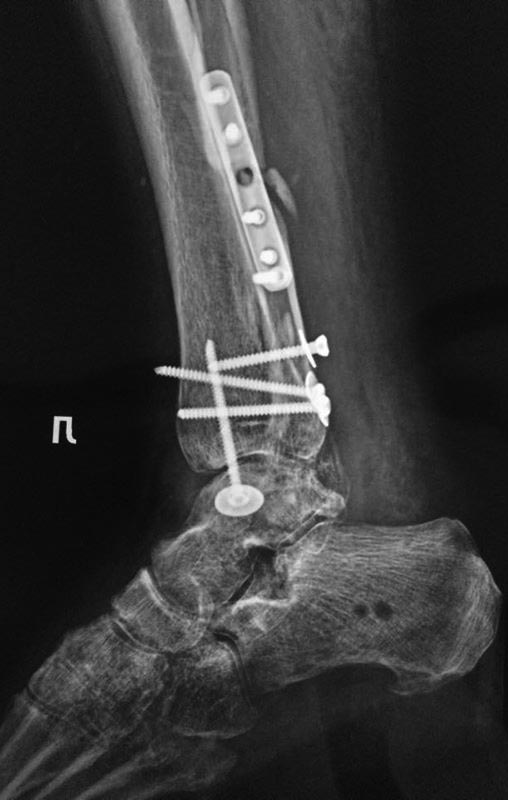

А вот такую задачку нам задали друзья с севера. Операция в мае этого

года. На данный момент пациент опереться на конечность не может.

Возраст: за 50. Движений в голеностопном суставе практически нет ( в

пределах 10-15 градусов) суставы стопы функционируют. Умеренная

контрактура. Ходит с костылями, приступает на ногу. Нагрузка не по оси.

Внешний вид: застарелый отек.

Да, и забыл отметить. Обратите внимание на синтез заднего края. Доступ с

отсечением ахилла